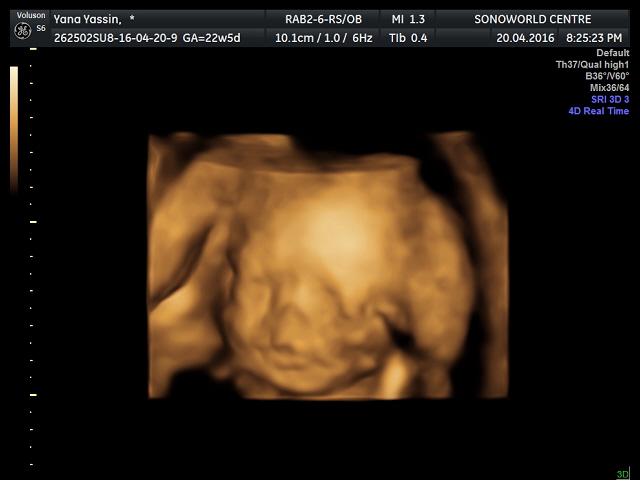

Yang berwarna nie 3D / 4D Scan

YY bukan setakat buat detail scan , sambung pulak dengan 3D / 4D scan . Dari 3D/4D scan , kita bleh tau jantina kandungan . Tapi apa kan daya , adik Kak long Qaireen nie pemalu sangat , muka pun payah nak tunjuk , jantina pun nak sorok . Malu - malu eh nak tunjuk .